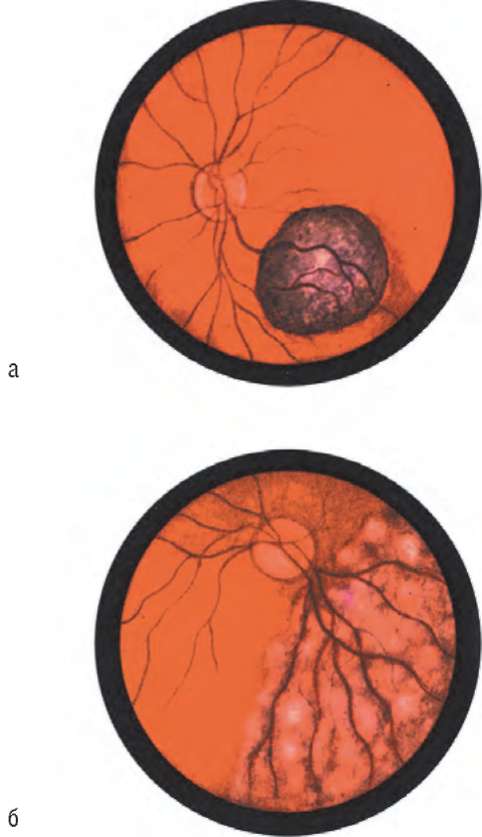

Рис. 19.7. Саркома внутри глазного яблока (а, б - варианты офтальмоскопической картины)